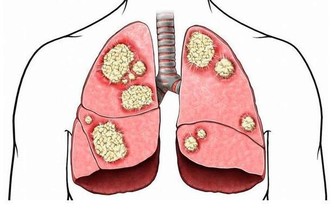

3、損傷腎臟

痛風患者體內的尿酸比較高,大量的尿酸鹽在腎臟內沉積,最終導致腎病變。據WHO統計,1/4的痛風患者會出現腎功能衰竭,發展為嚴重的尿毒症。